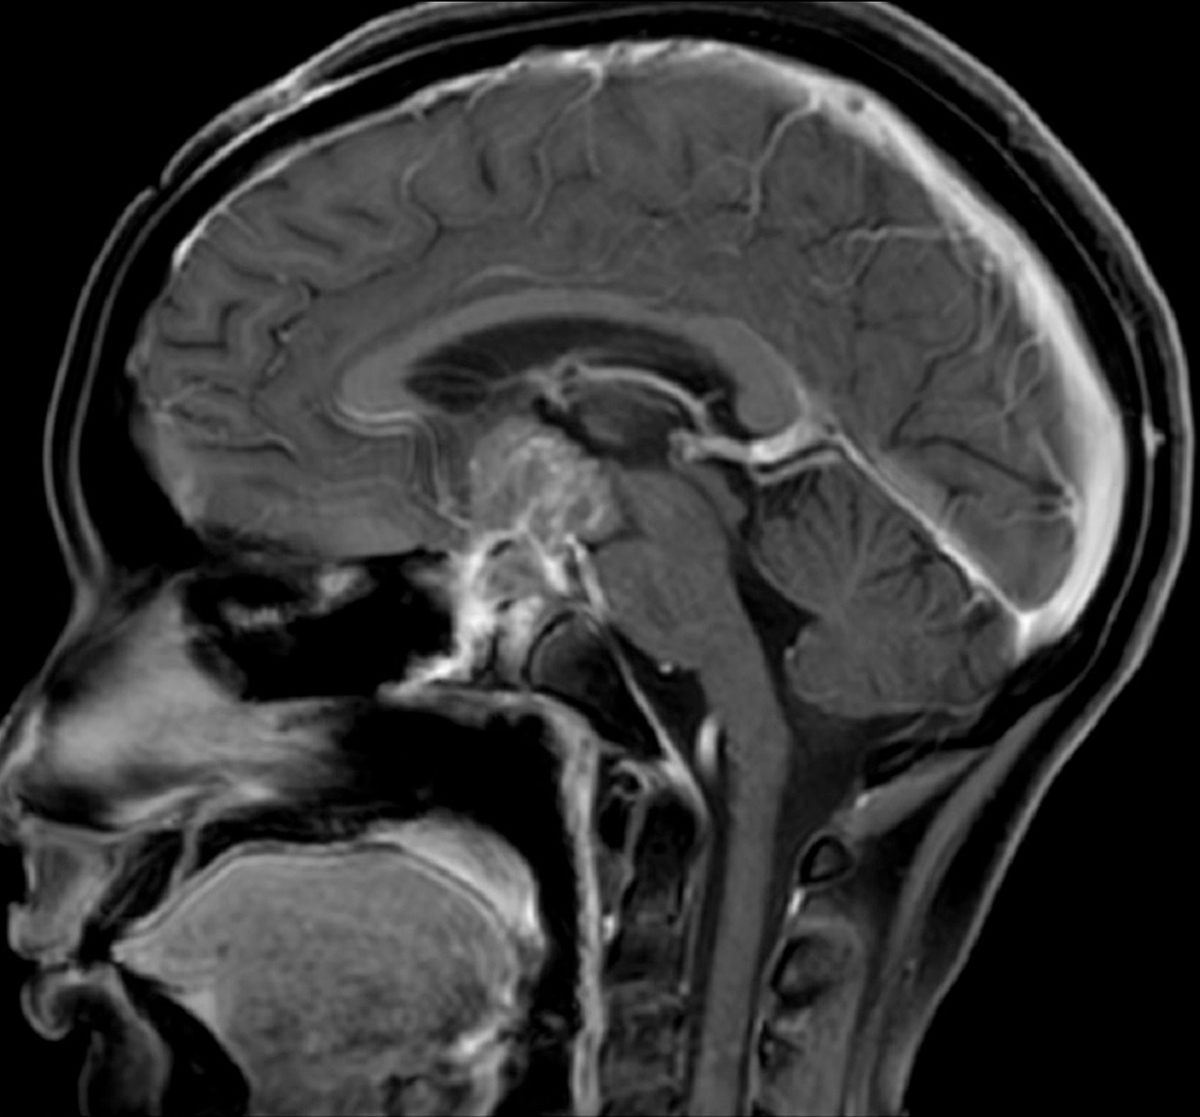

Telerradiologia,